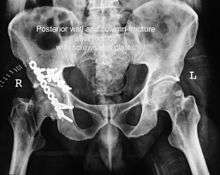

Posterior column with posterior wall / Transverse with posterior wall Fractures

These fractures are extension of elementary fractures. With involvement of posterior wall, the difficulty in treatment increases. These fractures are rarely amenable to non-surgical treatment. Due to posterior wall fracture, the hip is usually dislocated posteriorly, requiring immediate reduction of dislocation and surgical reconstruction after few days.

Cause: Posterior column with posterior wall fracture occurs due to dash board injury, while transverse fracture with posterior wall fracture occurs due to combined dash board injury and direct injury to the hip from the side.

In some cases traction for six to eight weeks may be the only treatment required

If the fragments do not fall into place, or if there are bone pieces in the joint, or if the joint is unstable, surgical fixation using screw(s) and plate(s) is performed

Post-surgery treatment: depending on the stability achieved, the person may be allowed standing and walking with help of support for about six to eight weeks.

Full function may return in about three months.